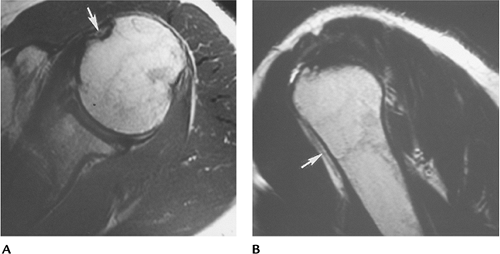

![]() |

FIGURE 7-39 Coronal (A) axial (B) MR images in a patient with a subscapularis tear and dislocation of the biceps tendon (arrow).

P.497

FIGURE 7-40 Axial T1-weighted (A) and sagittal T2-weighted image (B) showing a thinned atrophic biceps tendon (arrow).